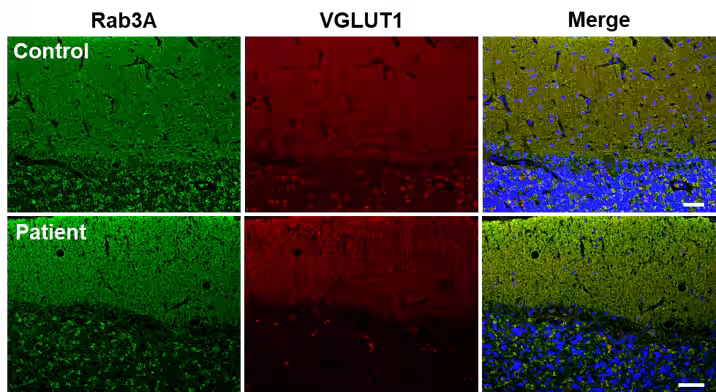

2. 小脳の病理分析

脳の剖検による分析では、プルキンエ細胞の著しい減少を伴う小脳皮質の変性が確認され、Rab3Aが平行線維に集中的に存在することが示されました。